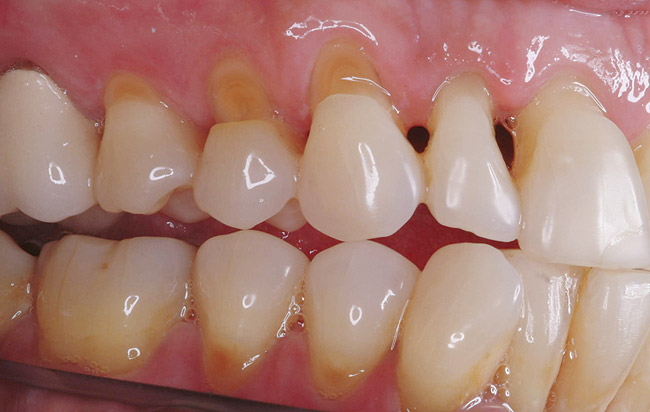

Fig. 10 Non-carious cervical lesions are evident in both arches.

Figure 10  Non-carious cervical lesions are evident in both arches.

Figure 10

Replacement of existing restorations is responsible for 75% of all operative dentistry.15,19 The reasons for placement and replacement of restorations of direct restorative materials include: primary caries (Figure 1 and Figure 2); recurrent caries (Figure 3); poor margins (Figure 4 and Figure 5); restoration fracture (Figure 6 and Figure 7); tooth fracture (Figure 8); esthetics (Figure 9); non-carious tooth structure lost (attrition, abrasion, abfraction, erosion) (Figure 10); and pain/sensitivity.